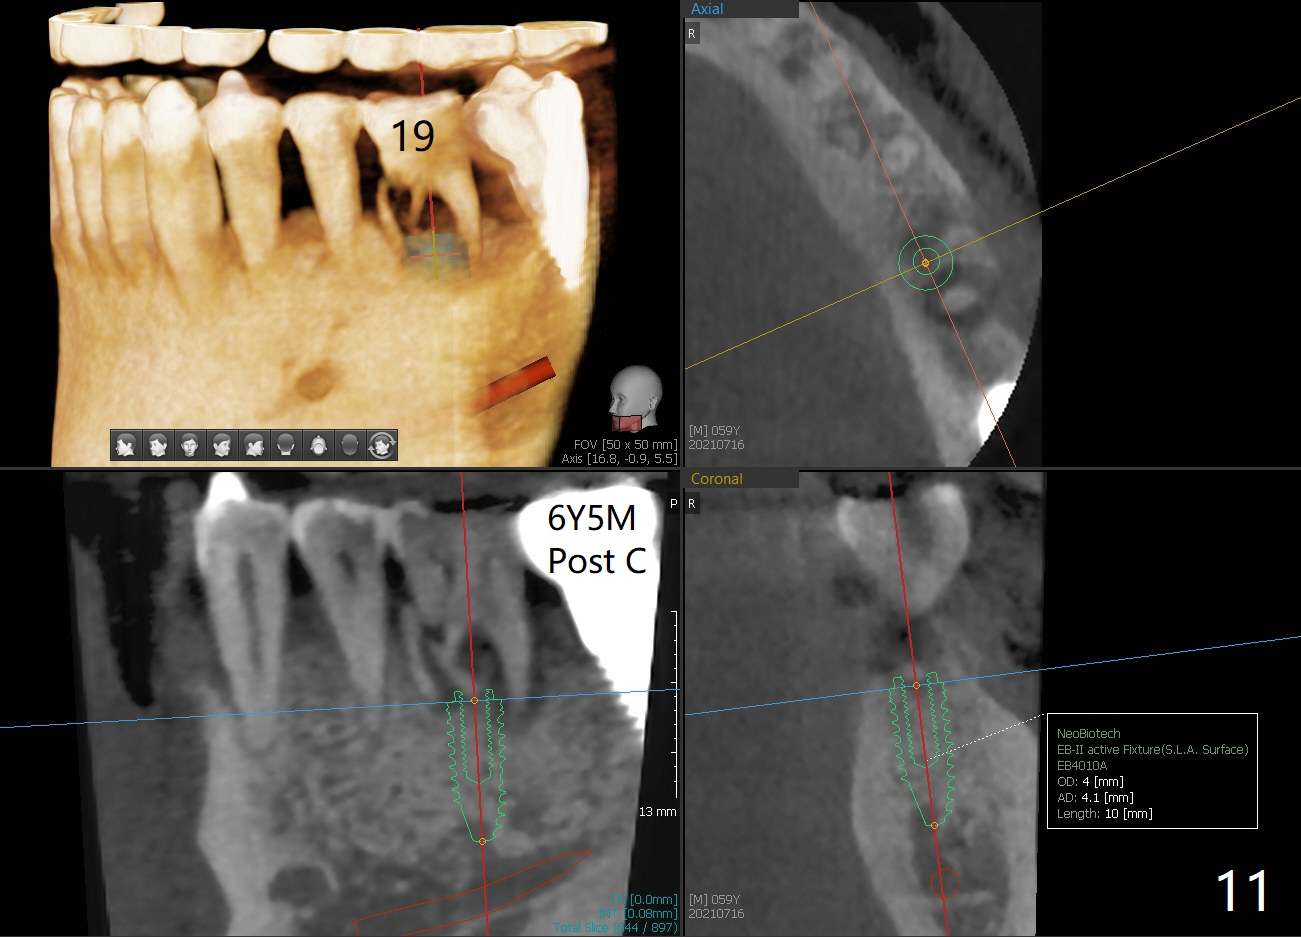

There is no bone resorption 6 months post cementation (12 months postop, Fig.8,9).  Mild bone resorption is observed 3 years post cementation (Fig.10).  It may be related to the large implant (7 mm) in association with chronic periodontitis and bruxism.   The roots of the teeth #19 and 30 fracture 6 years 5 months post cementation at #18 (Fig.11).  Since gingival recession is severe at #18 probably related to the large implant, the one at #19 will be designed small.